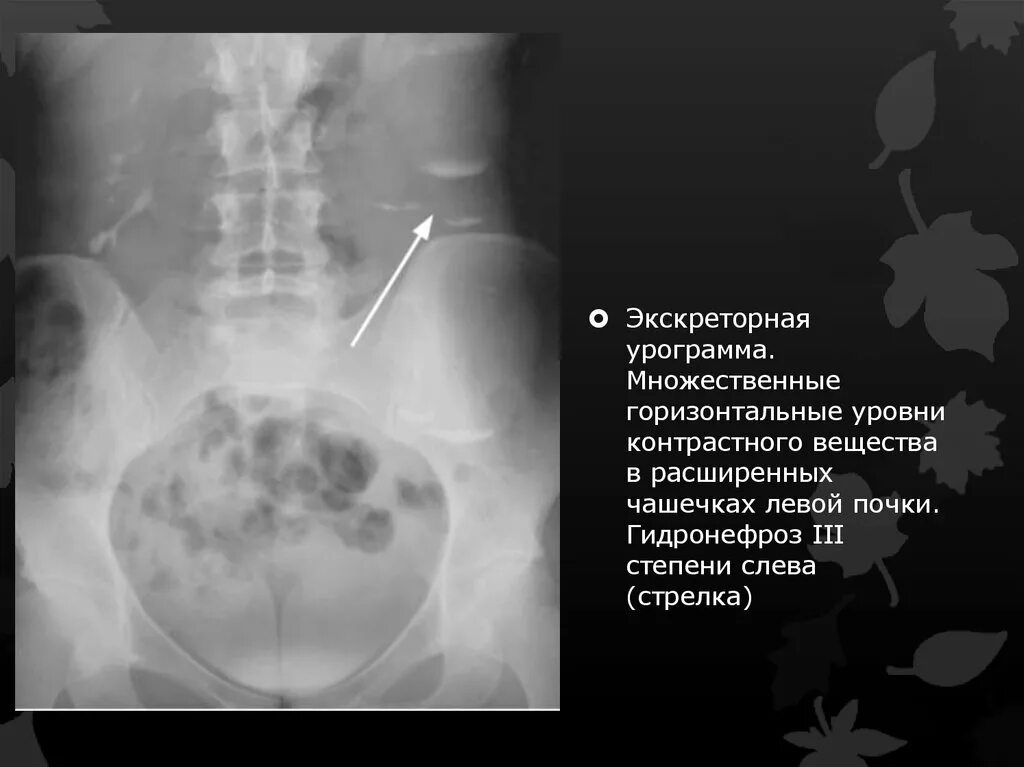

Гидронефроз 1 степени